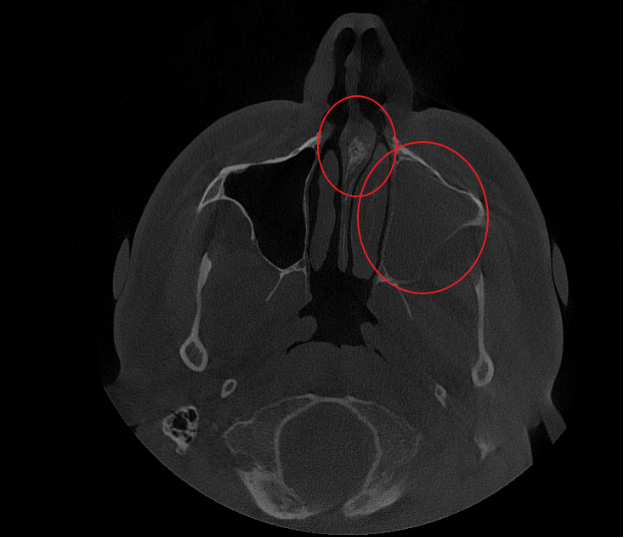

- Компьютерная томография (КЛКТ) околоносовых пазух и височных костей: Этот высокоинформативный метод диагностики объективно показал искривление носовой перегородки вправо, субтотальное снижение пневматизации (воздушности) левой верхнечелюстной пазухи, что свидетельствовало о хроническом воспалительном процессе. Костно-деструктивных изменений не выявлено.

- Хронический левосторонний верхнечелюстной синусит (J32.0). Длительное воспаление слизистой оболочки левой гайморовой пазухи, подтвержденное КТ.

Послеоперационный период протекал гладко. Проводились регулярные туалеты полости носа, промывание оперированной пазухи, назначались средства для увлажнения и регенерации слизистой оболочки, а также местная антибактериальная терапия. По результатам оперативного лечения носовое дыхание было полностью восстановлено, признаки активного воспаления купированы. Спустя 1.5 месяца после проведенного оперативного лечения проведено КТ околоносовых пазух в динамике, что отражает промежуточный результат оперативного лечения. На снимках: Перегородка носа располагается по центру, оперативно созданное соустье левой верхнечелюстной пазухи функционирует, пневматизация левой верхнечелюстной пазухи значительно улучшилась. Окончательный результат можно будет оценить через 3 месяца после проведенной операции, и при полной пневматизации левой верхнечелюстной пазухи пациент сможет приступить к установке зубных имплантов в верхнюю челюсть слева.